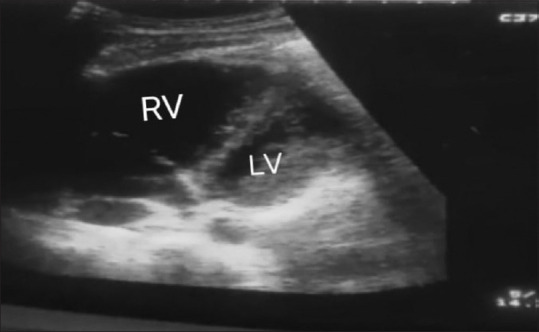

Abstract: Acute massive pulmonary thromboembolism (PTE) is a potentially life-threatening condition requiring urgent management to decrease mortality. However, in the peripheral setting, managing the emergency can be challenging. We report a case of massive PTE presenting with cardiopulmonary arrest, successfully managed with advanced cardiac life support, early initiation of anticoagulants (heparin), and thrombolytics. This case report explores the successful management of a critically ill patient presenting with massive pulmonary embolism in a peripheral healthcare facility, emphasizing the importance of a well-coordinated approach in such challenging environments. The approach in the case included recognizing the challenge with timely provisional diagnosis, initial stabilization, hemodynamic support, early consideration for anticoagulants, and thrombolysis after supporting provisional diagnosis with point-of-care ultrasonography (POCUS), team effort, and administrative support in Cas Evac to the tertiary care center. Timely administration of heparin and thrombolytics may serve as potential life-saving measures in peripheral settings, along with the availability of an ultrasound machine. Managing acute life-threatening massive PTE in peripheral settings requires a strategic and resourceful approach. Timely administration of heparin and thrombolytics may serve as potential life-saving measures. However, the administration of thrombolytics in PTE needs the support of POCUS to make quick decisions in peripheral settings. Collaboration between peripheral and advanced tertiary care healthcare facilities is crucial to ensure optimal outcomes for patients experiencing this critical condition.